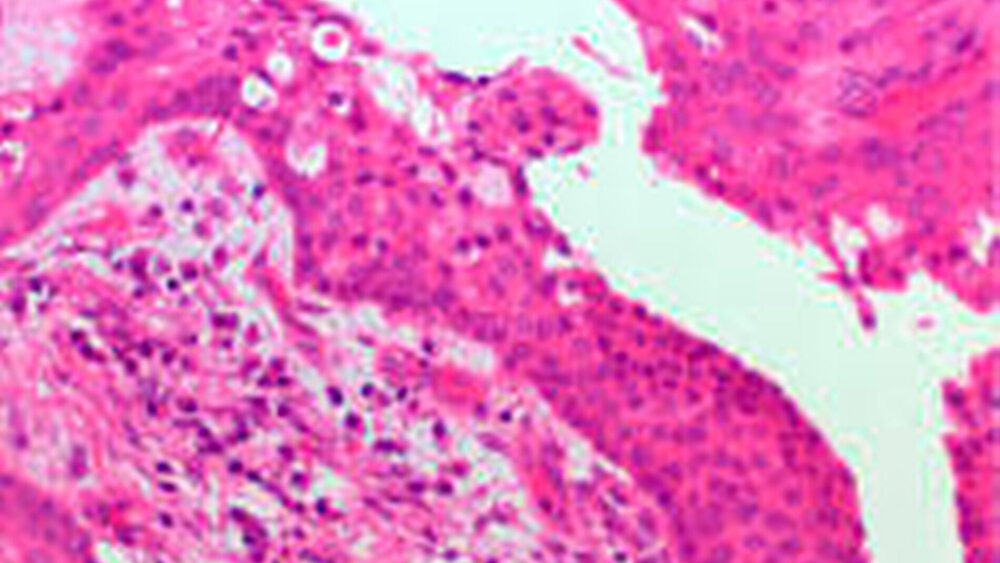

Die Entnahme einer Gewebeprobe ergab nach pathohistologischer Untersuchung eine glanduläre odontogene Zyste (GOC). Die Gewebeschnitte zeigen nicht keratinisiertes squamöses Epithel unterschiedlicher Dicke. Die superfizielle Zellschicht besteht aus kubischen bis prismatischen Zellen. Das lumenständige Epithel enthält häufig invaginiertes Epithel und Microzysten.

In den Mikrocysten ist ein PAS-positives, diastase-resistentes und Alcian-Blau positives muzinöses Sekret. Umgeben wird das Zystenlumen von einer fibrösen Kapsel.

Histologisch ist die GOC dadurch charakterisiert, dass sie in weiten Bereichen von einem stratifizierten squamösen Epithel bedeckt wird. Innerhalb des Epithels können schleimproduzierende Zellen auftreten, die von mit Schleim gefüllten Krypten unterbrochen sind. Einige Zellen können auch Zilien besitzen [20]. Gelegentlich treten kleine Mikrozysten auch innerhalb des Epithels auf, wobei Kalzifikationen nachweisbar sind [19]. Bei der dargestellten Zystenentität sollte berücksichtigt werden, dass sie am Anfang häufig eine parodontale multilokuläre Radioluzenz aufweist [22]. Die Diagnose ist ausschließlich mikroskopisch möglich.